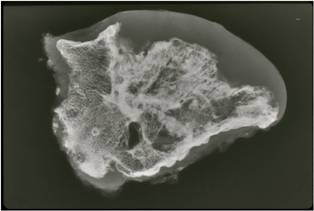

Pathology

Pathology:

- Medullary and cortical continuity w/ underlying bone

- Hyaline Cartilage Cap with lobular growth

Gross Pathology

- The osteochondroma is completely covered in periosteum

- Cut surface shows hyaline composition of cartilage cap

Cap

- Younger patients thicker cap because of growth hormone

- Smooth or knobby

- 2 mm to 1 cm thick

Beneath the cap, calcified cartilage which appear as white deposits are present